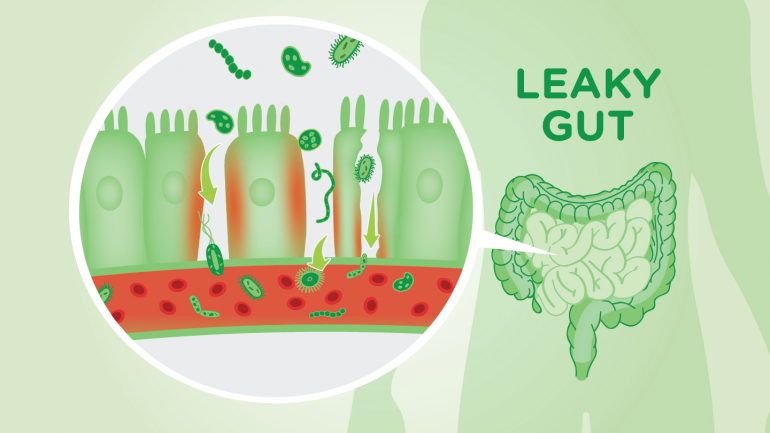

Πώς ένα κοινό διατροφικό συστατικό μπορεί να οδηγήσει σε αρθρίτιδα

Η εργασία καταλήγει στο συμπέρασμα ότι ο αποκλεισμός της δημιουργίας ινδόλης μπορεί να παρουσιάσει μια μοναδική θεραπευτική οδό για τη ρευματοειδή αρθρίτιδα και τη σπονδυλαρθρίτιδα.